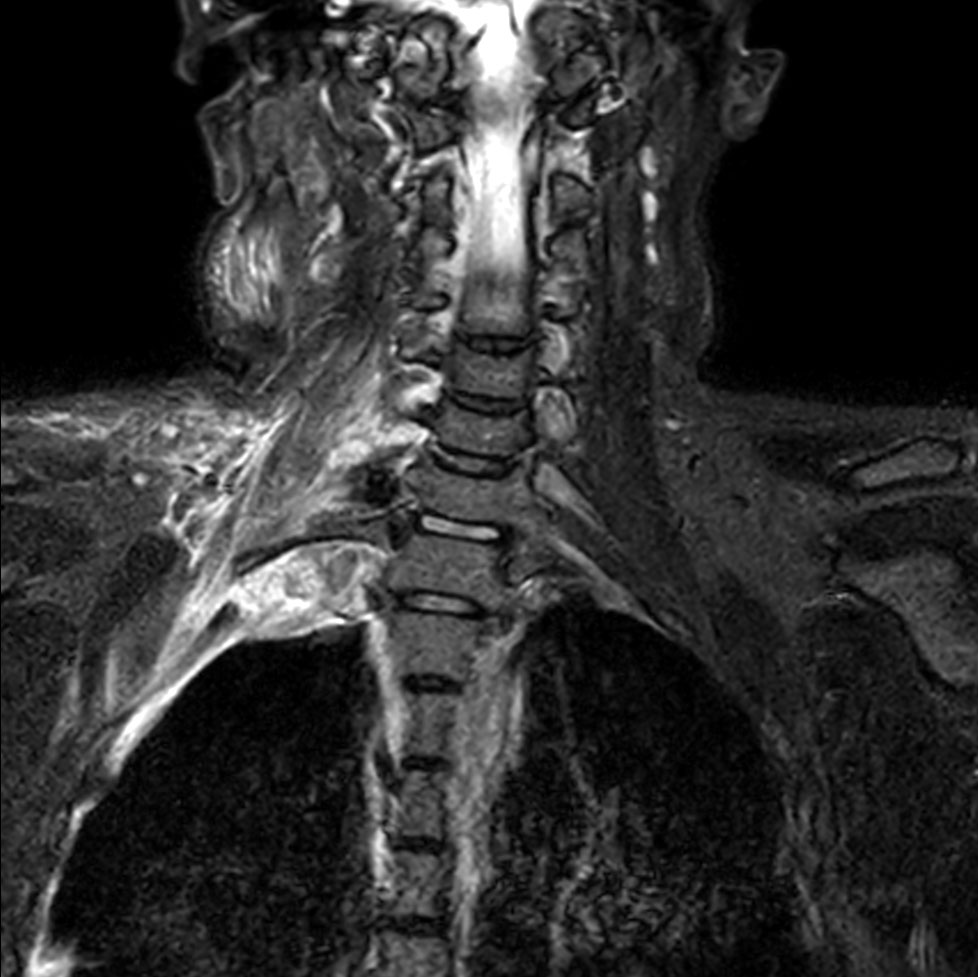

Coronal STIR TSE